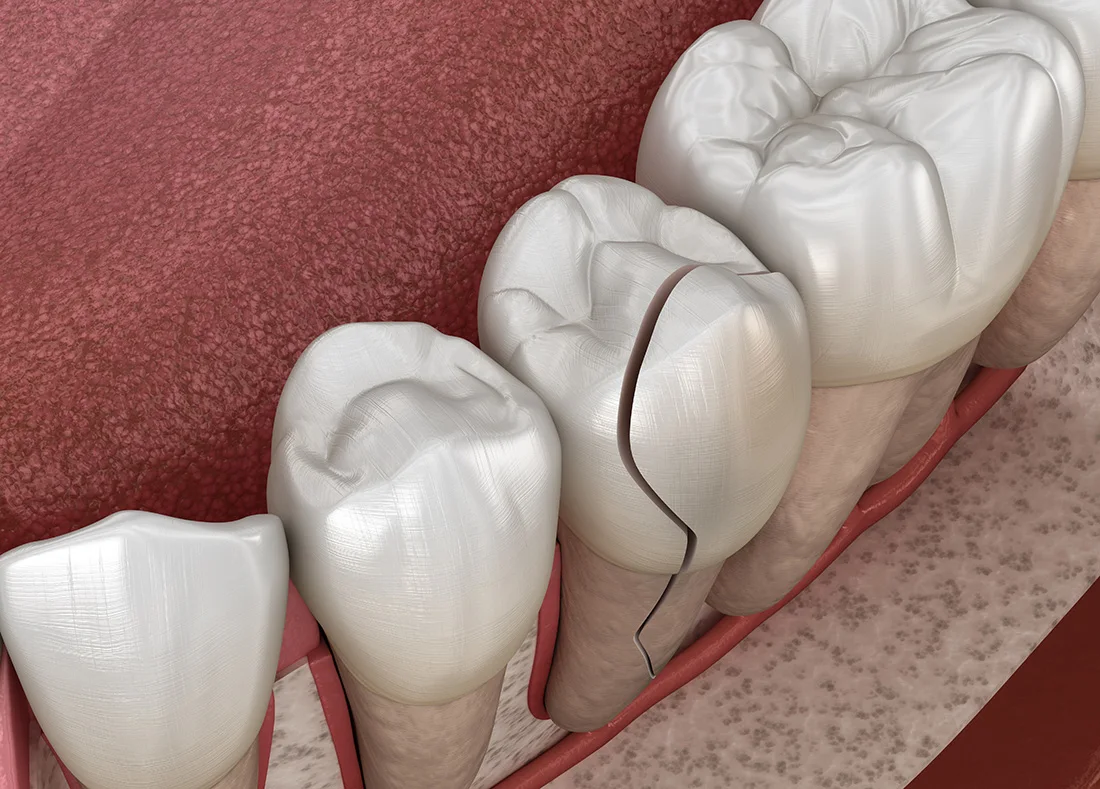

If your tooth has been knocked loose from trauma or an accident, you may still have a chance to save it—but you need to act fast. Refrain from wiggling or pressing on the tooth with your fingers or tongue, as this can worsen the injury. Call our office right away. If treated early, we can often stabilize the tooth with a splint and give it time to heal and reattach to surrounding bone and gum tissue. Waiting too long could lead to tooth loss, so don’t delay reaching out.